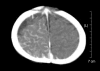

Sturge-Weber syndrome can be associated with facial port-wine stains and intracranial calcification, and concurrent Klippel-Trenaunay-Weber syndrome has been reported. Klippel-Trenaunay-Weber syndrome is a rare congenital mesodermal phakomatosis characterized by cutaneous hemangiomas, venous varicosities and soft tissue or bone hypertrophy of the affected extremities. This report is presented a rare case of the Sturge-Weber syndrome in combination with the Klippel-Trennaunay syndrome and phakomatosis pigmentovascularis in a 4-month-old infant. He showed nevus flameus on the right leg and both part of the face and back, leptomeningeal angiomatosis on right hemisphere, hypertrophy of the right leg, hemiconvulsion on the left and also evidences of congenital glaucoma and nevus of Ota. Very rare case combined with these three kinds of phakomatosis has been reported.